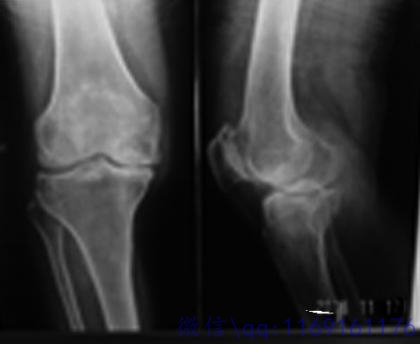

膝关节部位受到外伤等因素的影响,导致其内部出现病变,很容易使得该关节出现骨质增生,从而影响人们的正常活动,为此,人们应做好日常的预防工作。

骨刺在临床上被称为骨质增生,它是高发于中老年人群,当其发生在膝关节部位,患者常出现膝关节酸痛、活动不便等表现,给大家的健康和生活都造成一定困难。人们应认识到,骨质增生可防可治。下面就为大家介绍一下,如何才能避免患上膝关节骨刺?

膝盖骨质增生CT图 (12).jpg